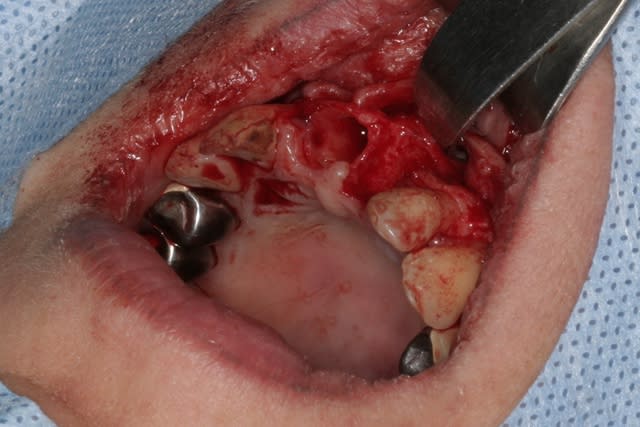

Purée, tu prends des risques énormes en fourrant ton bio oss puis en vissant les implants dans la masse de bio oss, de un, et sans membraner l'interface pilier implant, de deux...

Je suis peut-être vieux jeu mais c'est, à mon avis, dangereux d'un point de vue bactériologique.

c'est pas la première fois que je fais çà...;-)

et çà me donne plutôt de bons résultats

après tout...le périoste n'est-il pas la meilleure membrane?

par contre il faut veiller à avoir une bonne étanchéité au niveau des sutures...